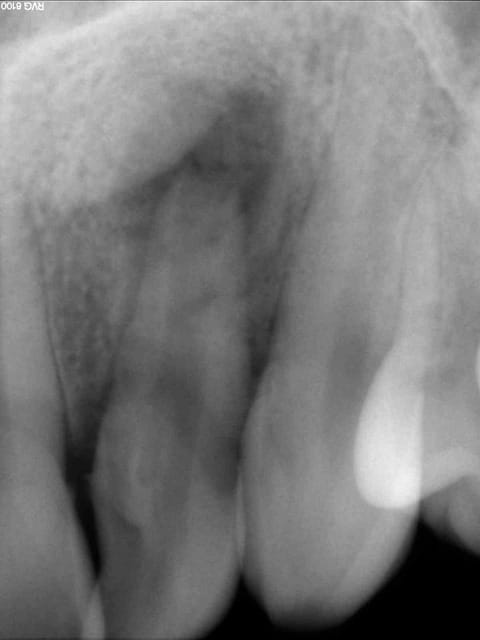

photos jointes: cas de resorption externe avec à l'origine faux canal, félure ou juste la resorption qui avait atteint le canal...

Obturée à la biodentine allongée, pose de srew post titane dans la foulée de l'obturation, un moignon compo a été réalisé ensuite.

Dent traitée en urgence (abcès), ça saignait mais j'ai pu cauteriser (merci lokki), une galère si j'avais voulu mettre de la gutta.... perdue pour perdue j'ai tenté le truc, c'était en janvier 2014 et la dent, recoiffée depuis est toujours là, asymptomatique.

La patiente est prevenue que ça tiendra ce que ça tiendra et qu'elle doit faire des economies pour eventuel implant à venir (ou vacances avec son copain si l'implant tarde à venir).